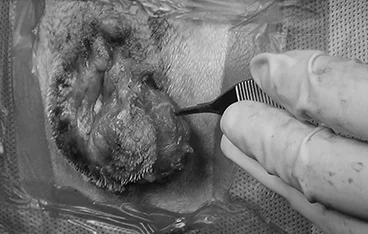

담낭점액종

담낭절제술 + 담관 Flushing

• 담낭절제술